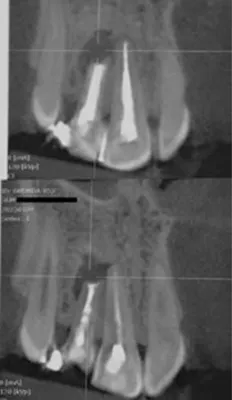

FIG 2:

CBCT of the patient indicates to an unsalvageable tooth.

FIG 3:

This sectional image from the CBCT shows the extent of bone damage caused by the lesion.